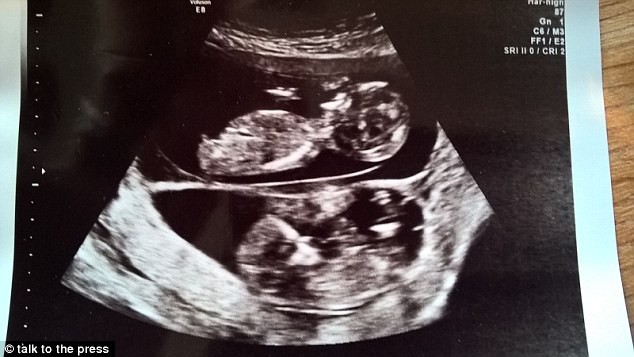

Susie nói: “Tôi không thể ngờ mình lại mang thai nhanh như vậy, tôi vừa mới sinh bé Hendrix được 6 tháng. Ngay ở lần đầu siêu âm, các bác sĩ đã nhận thấy được sự khác biệt về kích thước của 2 cái thai, nhưng đến lần thứ 2, khoảng 12 tuần sau, họ nói rằng hai cái thai cách nhau khoảng 10 ngày”. Hai thai nhi rất khỏe mạnh và phát triển bình thường.

Susie đã hạ sinh hai bé tại bệnh viện Wrexham Park, Slough. Bé gái Leni nặng 1,7 kg và anh trai của bé, Jenson nặng 2,1 kg. Hai bé đã được về nhà sau 10 ngày chăm sóc đặc biệt tại bênh viện.